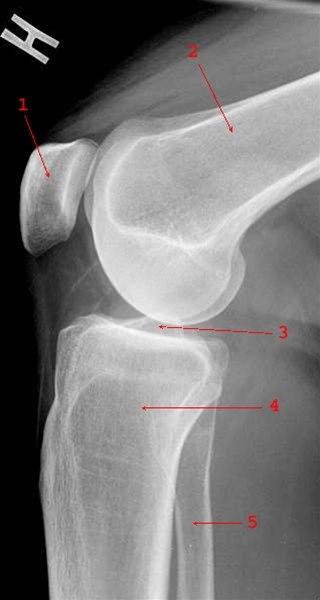

Røntgenbilde av kneleddetKneleddet utgjøres av lårbeinets og leggbeinets leddflater. Beinvevet er kledd med brusk som gjør at leddflatene glir mot hverandre med minst mulig motstand. I tillegg har kneleddet to bruskskiver (meniskene) som fremmer bevegeligheten i leddet. Artrose i kneleddet er den vanligste type revmatisk leddsykdom. Forandringer i leddbrusk og bein i leddet gjør at overflatene ikke lenger er glatte og symmetriske. Tidligere kaltes dette slitasjegikt. Begrepet er misvisende og brukes derfor ikke lenger.

Røntgen av kneet er vanligvis ikke nødvendig for å stille diagnosen. Hos personer som er 45 år eller eldre, har smerte i kneleddet som er relatert til fysisk aktivitet og ikke har morgenstivhet eller kun morgenstivhet med varighet opptil en halvtime, kan legen stille diagnosen uten å bestille tilleggsundersøkelser. Ved mistanke om andre underliggende årsaker kan det tas et røntgenbilde (stående), som kan bekrefte lette, moderate eller uttalte artroseforandringer.

Røntgenbildene forteller likevel ikke hele sannheten, fordi det kan være manglende samsvar mellom graden av plager og graden av forandringer på røntgen. Svært tidlige artroseforandringer kan ikke alltid påvises hos pasienter med begynnende plager. Motsatt kan pasienter med påviste røntgenforandringer ha beskjedne eller ingen symptomer. Tilleggsundersøkelser vil være nødvendig dersom symptombildet avviker fra det som forventes ved kneleddsartrose eller hvis pasienten henvises til vurdering av operasjon.